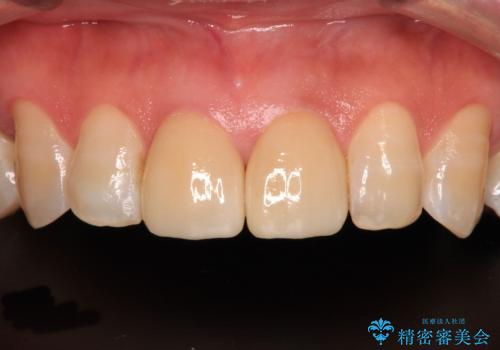

- 上顎4前歯に装着されているセラミッククラウンのうち、ひとつが欠けてしまったとのことで来院された患者様です。

土台となっている歯には問題がないため、周囲のセラミッククラウンと色調が合うように、オーダーメイドタイプのセラミッククラウンにて補綴治療を行うこととしました.

欠けてしまったセラミッククラウンはガラス系セラミッククラウンであったため、今回製作する歯は、強度の強いジルコニアセラミッククラウンとしました。

クラウンの種類は異なりますが、色調の適合したクラウンを装着することができました。